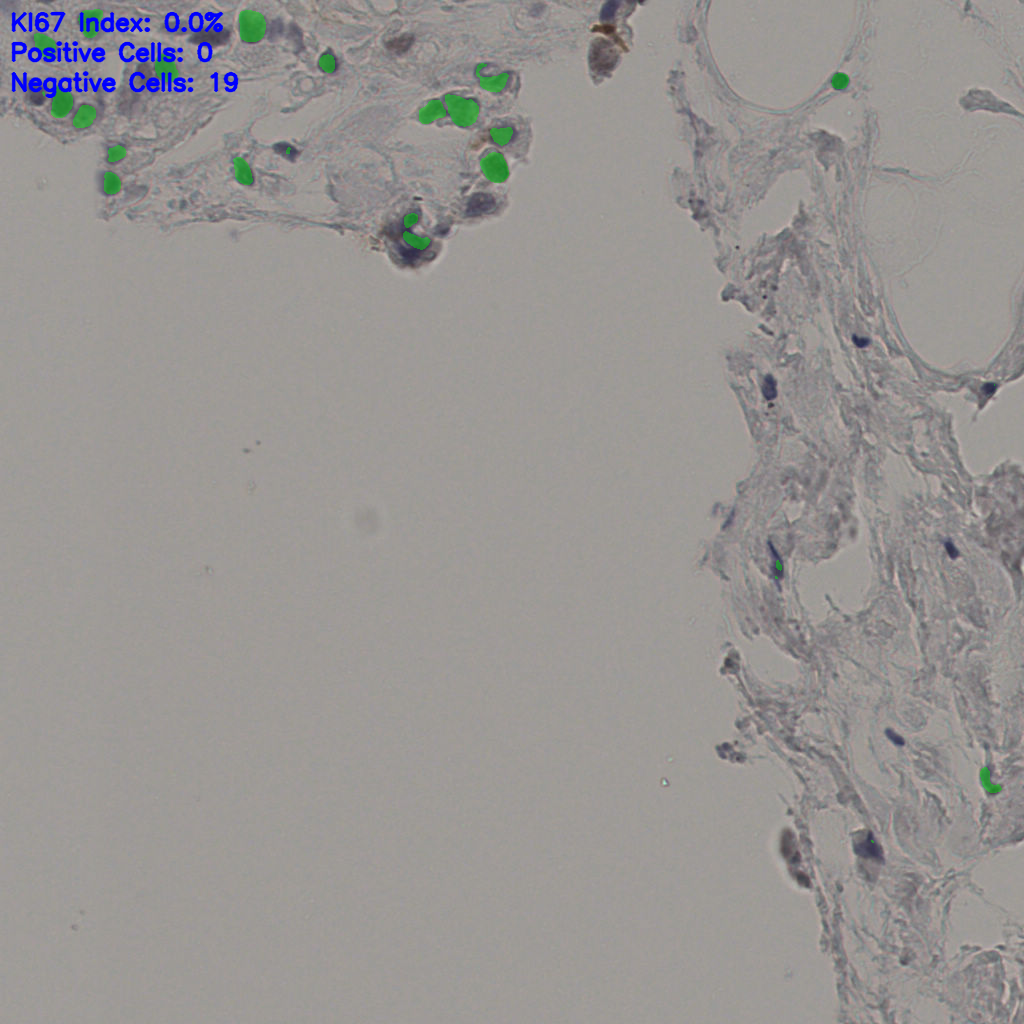

5.31%

Ki67 指数

阴 19502 阳 1093

总切片 2970

有效 554

已标记 554

有效率 19%